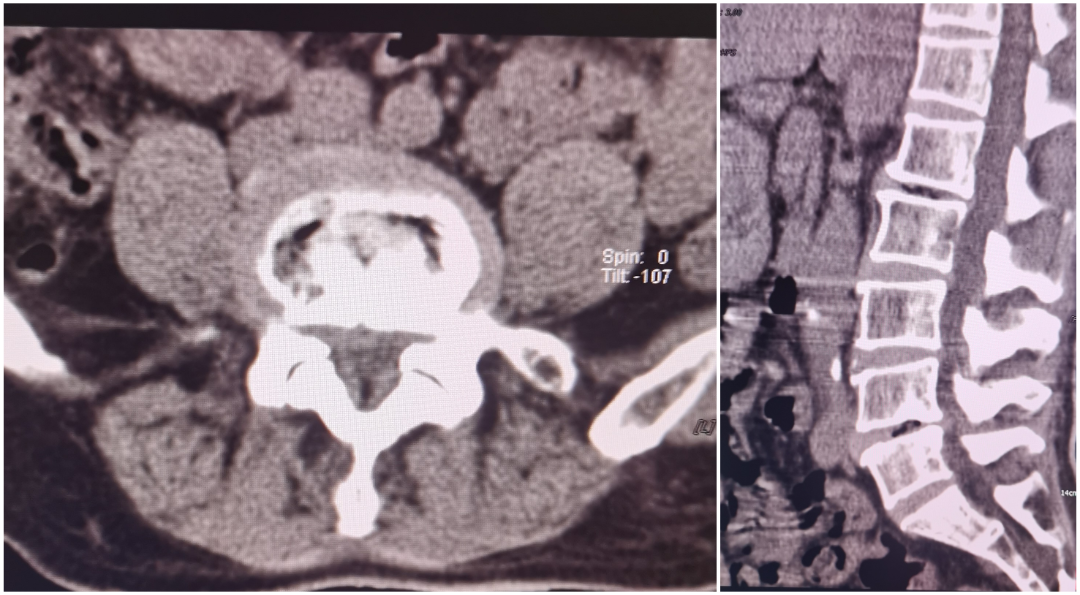

腰椎微创融合(MIS-TLIF)

患者陈某,中年女性,反复腰痛9年余,加重伴左下肢放射痛、麻木1月入院,查体:脊柱生理弯曲存在,腰部未扪及台阶感,腰椎间隙稍压痛,椎旁肌压痛及叩击痛,左下肢稍萎缩,左下肢肌力4级,左大腿、小腿外侧及足背外侧感觉麻木,左侧膝反射及跟腱反射减弱,右下肢肌力感觉正常,双下肢肌力正常,结合辅助检查,诊断:腰4/5椎间盘突出症,于全麻行MIS-TLIF入路腰4/5髓核摘除、椎管扩大减压神经根松解、椎间融合器植骨融合内固定术,术后第二天佩戴护具下床活动,恢复良好。

术前影像学

术后影像学检查